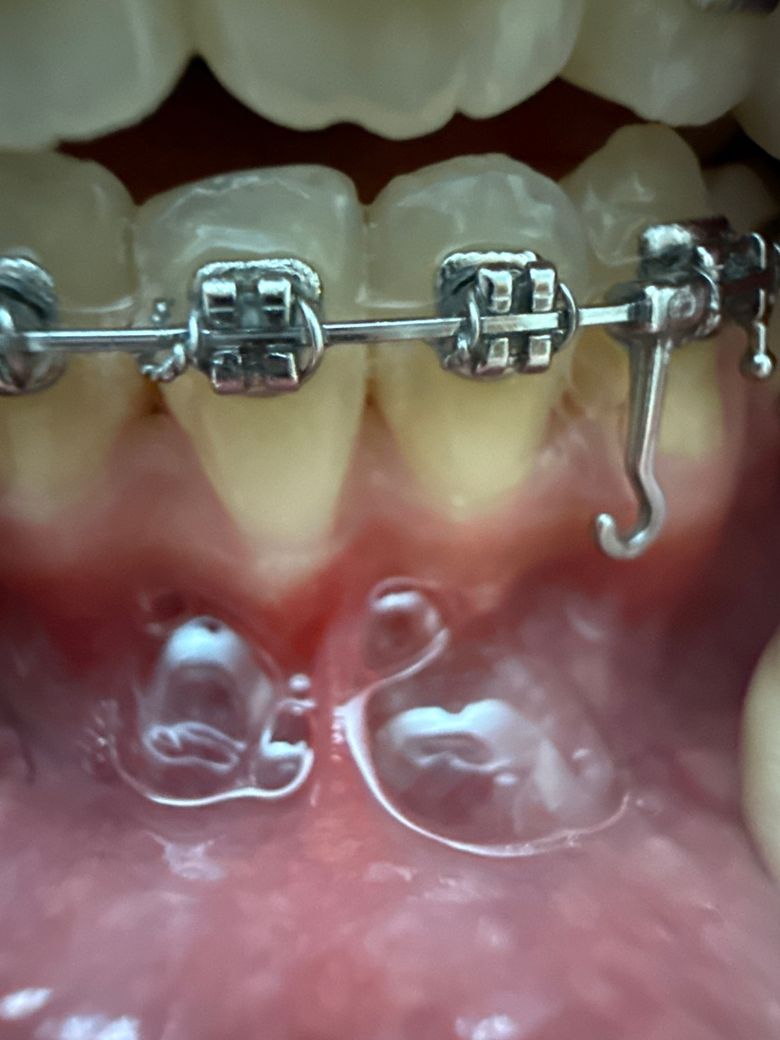

치아퇴축 뿌리가 너무 길게 보이는ㄴ거같아요

제가 교정받기전부터 이렇게 치아뿌리부분까지 좀 길긴했는데 이정도면 치아퇴축이 심한편인건가요? 저 18살입니다.....

위의 사진만 봤을 때에는 치아의 잇몸 퇴축이 심한 정도는 아닌 것 같습니다. 관리 잘해주시면 됩니다.

18살 치고는 잇몸이 살짝 내려간거 같습니다 교정을 하게되면 힘을 받아서 그럴수 있으니 지금부터라도 잇몸 관리를 해주시는게 좋을것같습니다.

지금으로서는 치은퇴축이 아주 심한 편은 아니지만 교정이 아직 진행중이므로 추가적으로 잇몸이 낮아질 수도 있습니다